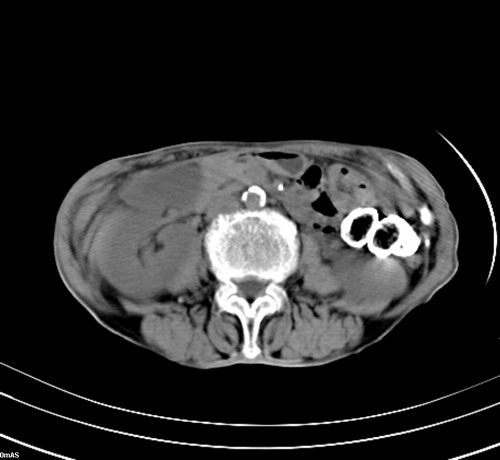

1 气管旁、隆突下淋巴结明显肿大,肝左叶外侧段低密影,都考虑转移。

2 肝右后叶下段明显增大,片状低密影,但因各种伪影显示不佳,不排除病变。

3 建议增强

后中纵隔团块影,伴气管、食道受压移位,首先考虑转移瘤,肝s5段低密度灶。建议增强检查,另外其结肠是否有问题请提供,右肺部分肺叶局限含气增多,考虑局限肺气肿。

后中纵隔团块影,伴气管、食道受压移位,首先考虑转移瘤,肝表现同11773。